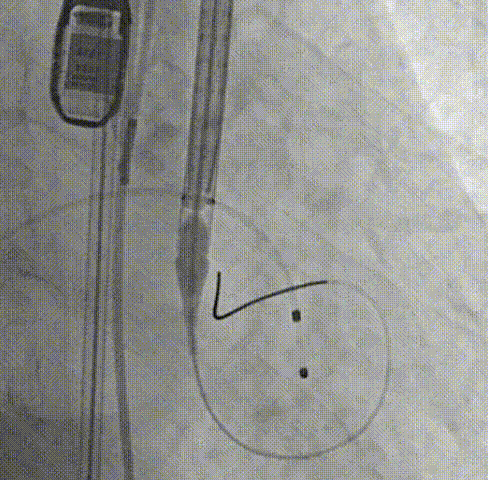

周达新教授 复旦大学附属中山医院 共识引路,干瓣启新,共赴临床解决方案:当前,结构性心脏病的介入治疗已迈入微创化、精准化的新时代。技术的革新、创新器械的上市,都是我们中国技术领跑的印证,《专家共识》的应运而生是中国医生对于行业“规范化”的践行,让治疗更精准、让医者更贴近“以患者为中心”的医疗本质。 潘文志教授 复旦大学附属中山医院 严谨求真重思考 创新临床互验证:在医学的漫长征途中,新器械的突破与严谨的临床研究是两大核心驱动力。拥抱创新的同时需要严谨求证,预装干瓣作为创新器械,其即取即用的特性可以很好的适配“急诊”的场景,此外,国产创新不是简单的复制,干瓣的瓣叶质地不是字面意思“干”的,而具“曲柔性”。所以,需要多看多测,才能全面了解一款产品。《经导管心脏瓣膜治疗术》的问世也是凝结着我们带着临床思维思考的结晶的“独家秘笈”,希望能够将“来时的路”变成未来行业同行者的“高效学习之路”! 患者病史 多病共存陷困境,主动脉瓣狭窄成 “首要威胁” 现病史:患者反复活动后胸闷2年余,无胸痛、心悸,无头晕、晕厥等不适,未予重视。患者轻微体力活动(快走、爬楼梯)即胸闷气促,静息及夜间无不适,无咳嗽、心悸等症状。为进一步诊疗收入我科,患病以来精神、食欲、睡眠、二便及体重均正常。 既往史: 2025年5月7日因小便不畅至外院住院病理穿刺确诊前列腺癌,期间检查心超提示主动脉瓣钙化伴重度狭窄,遂暂缓前列腺手术。2025年05月30日至我院就诊。 2025年5月20日开始服用比卡鲁胺片。患者血脂异常,长期服用丹参滴丸,麝香保心丸,心通颗拉。 手术史外伤史:10年前行肺手术,具体不详。否认外伤史。 入院检查 心电图提示:窦性心动过缓;ST-T改变; 心超显示:主动脉瓣钙化伴重度狭窄及轻度反流,Vmax 4.8m/s、PGmax 93mmHg、PGmean 47mmHg;左房增大,左室壁增厚。 冠状动脉CT造影:左前降支中段浅表心肌桥,主动脉瓣增厚伴重度钙化,主动脉粥样硬化。 术前CT 三叶瓣,中度钙化,主动脉根部直径25.4mm,LVOT直径23.5mm 双侧冠脉开口高度尚可,瓦氏窦尚可,ST尚可,升主尚可,冠脉风险小;中度钙化,心脏角度39.2°;心腔内径可,左室壁增厚。 外周走行尚可,全主动脉存在散在钙化,右侧穿刺点需避开钙化,血管内径可,血管内壁存在纤维增厚。 手术策略:右侧股动脉为主入路,使用20F大鞘;20球囊预扩,植入AV29瓣膜; 手术过程 主动脉根部造影 输送系统柔顺过弓 定位 缓慢释放瓣膜 造影观察 稳定脱钩 最终造影性钙位置良好,轻微瓣周漏 术后超声:轻度瓣周漏,术后平均压差11mmHg 出院前超声:平均压差11mmHg 在多基础疾病患者日益增多的当下,该病例也为临床提供重要启示:针对合并肿瘤、既往手术史的复杂瓣膜病患者,需通过多学科协作(心内科、肿瘤科、麻醉科等)全面评估病情,结合精准影像技术与适配器械,制定个体化手术方案,才能在保障安全的同时,实现最优疗效。 作为中国结构性心脏病领域的标杆学术活动,中国结构周 2025为这类高水平临床病例提供了交流平台,助力推动我国结构性心脏病诊疗技术持续创新,让更多复杂瓣膜病患者受益于精准医疗方案。 ProStyle A®预装干瓣——助力临床最优化解决方案: 轻松过弓,精准可控:该病例全主动脉存在散在钙化,右侧穿刺点需避开钙化,ProStyle A®较细的尺寸+柔顺的输送系统通过性能得到了很好的验证; 平稳释放:平衡的径向支撑力降低了释放过程中的张力,流入端小锥角设计能够迅速锚定贴边; 预装干瓣 便捷顺安:金仕生物专利抗钙化技术运用纳米技术去除组织内的细胞碎片和磷脂,封闭游离醛基,从根本上阻断了瓣膜钙化的多项因素,显著提升了瓣膜的耐久性;同时,相比较传统戊二醛保存方式,干式存储最大限度的保留心包的亲水亲油平衡,还原组织天然曲柔性,进一步保障了瓣叶开合,保证长期耐久性; 专家简介 葛均波 复旦大学附属中山医院(点击查看专家详细简历) 周达新 复旦大学附属中山医院(点击查看专家详细简历) 潘文志 复旦大学附属中山医院(点击查看专家详细简历) · END ·